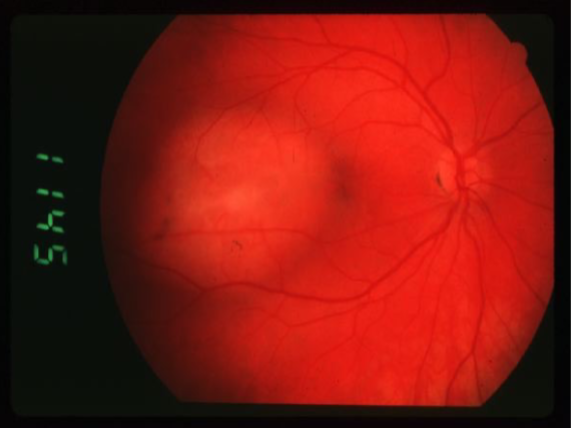

retinoblastoma

retinoblastoma

retinoblastoma

retinoblastoma

cancer affecting retinal photoreceptors

most common primary intraocular malignant tumor of childhood

ocular manifestations:

leukocoria

strabismus

dome-shaped lesion

whitish pink nodular mass

endophytic

retinoblastoma type

white, pearly-pink, creamy nodular mass that breaks through the ILM into vitreous

vitreous seeding

fine blood vessels on surface

secondary calcification leads to sharp demarcations (cottage cheese)